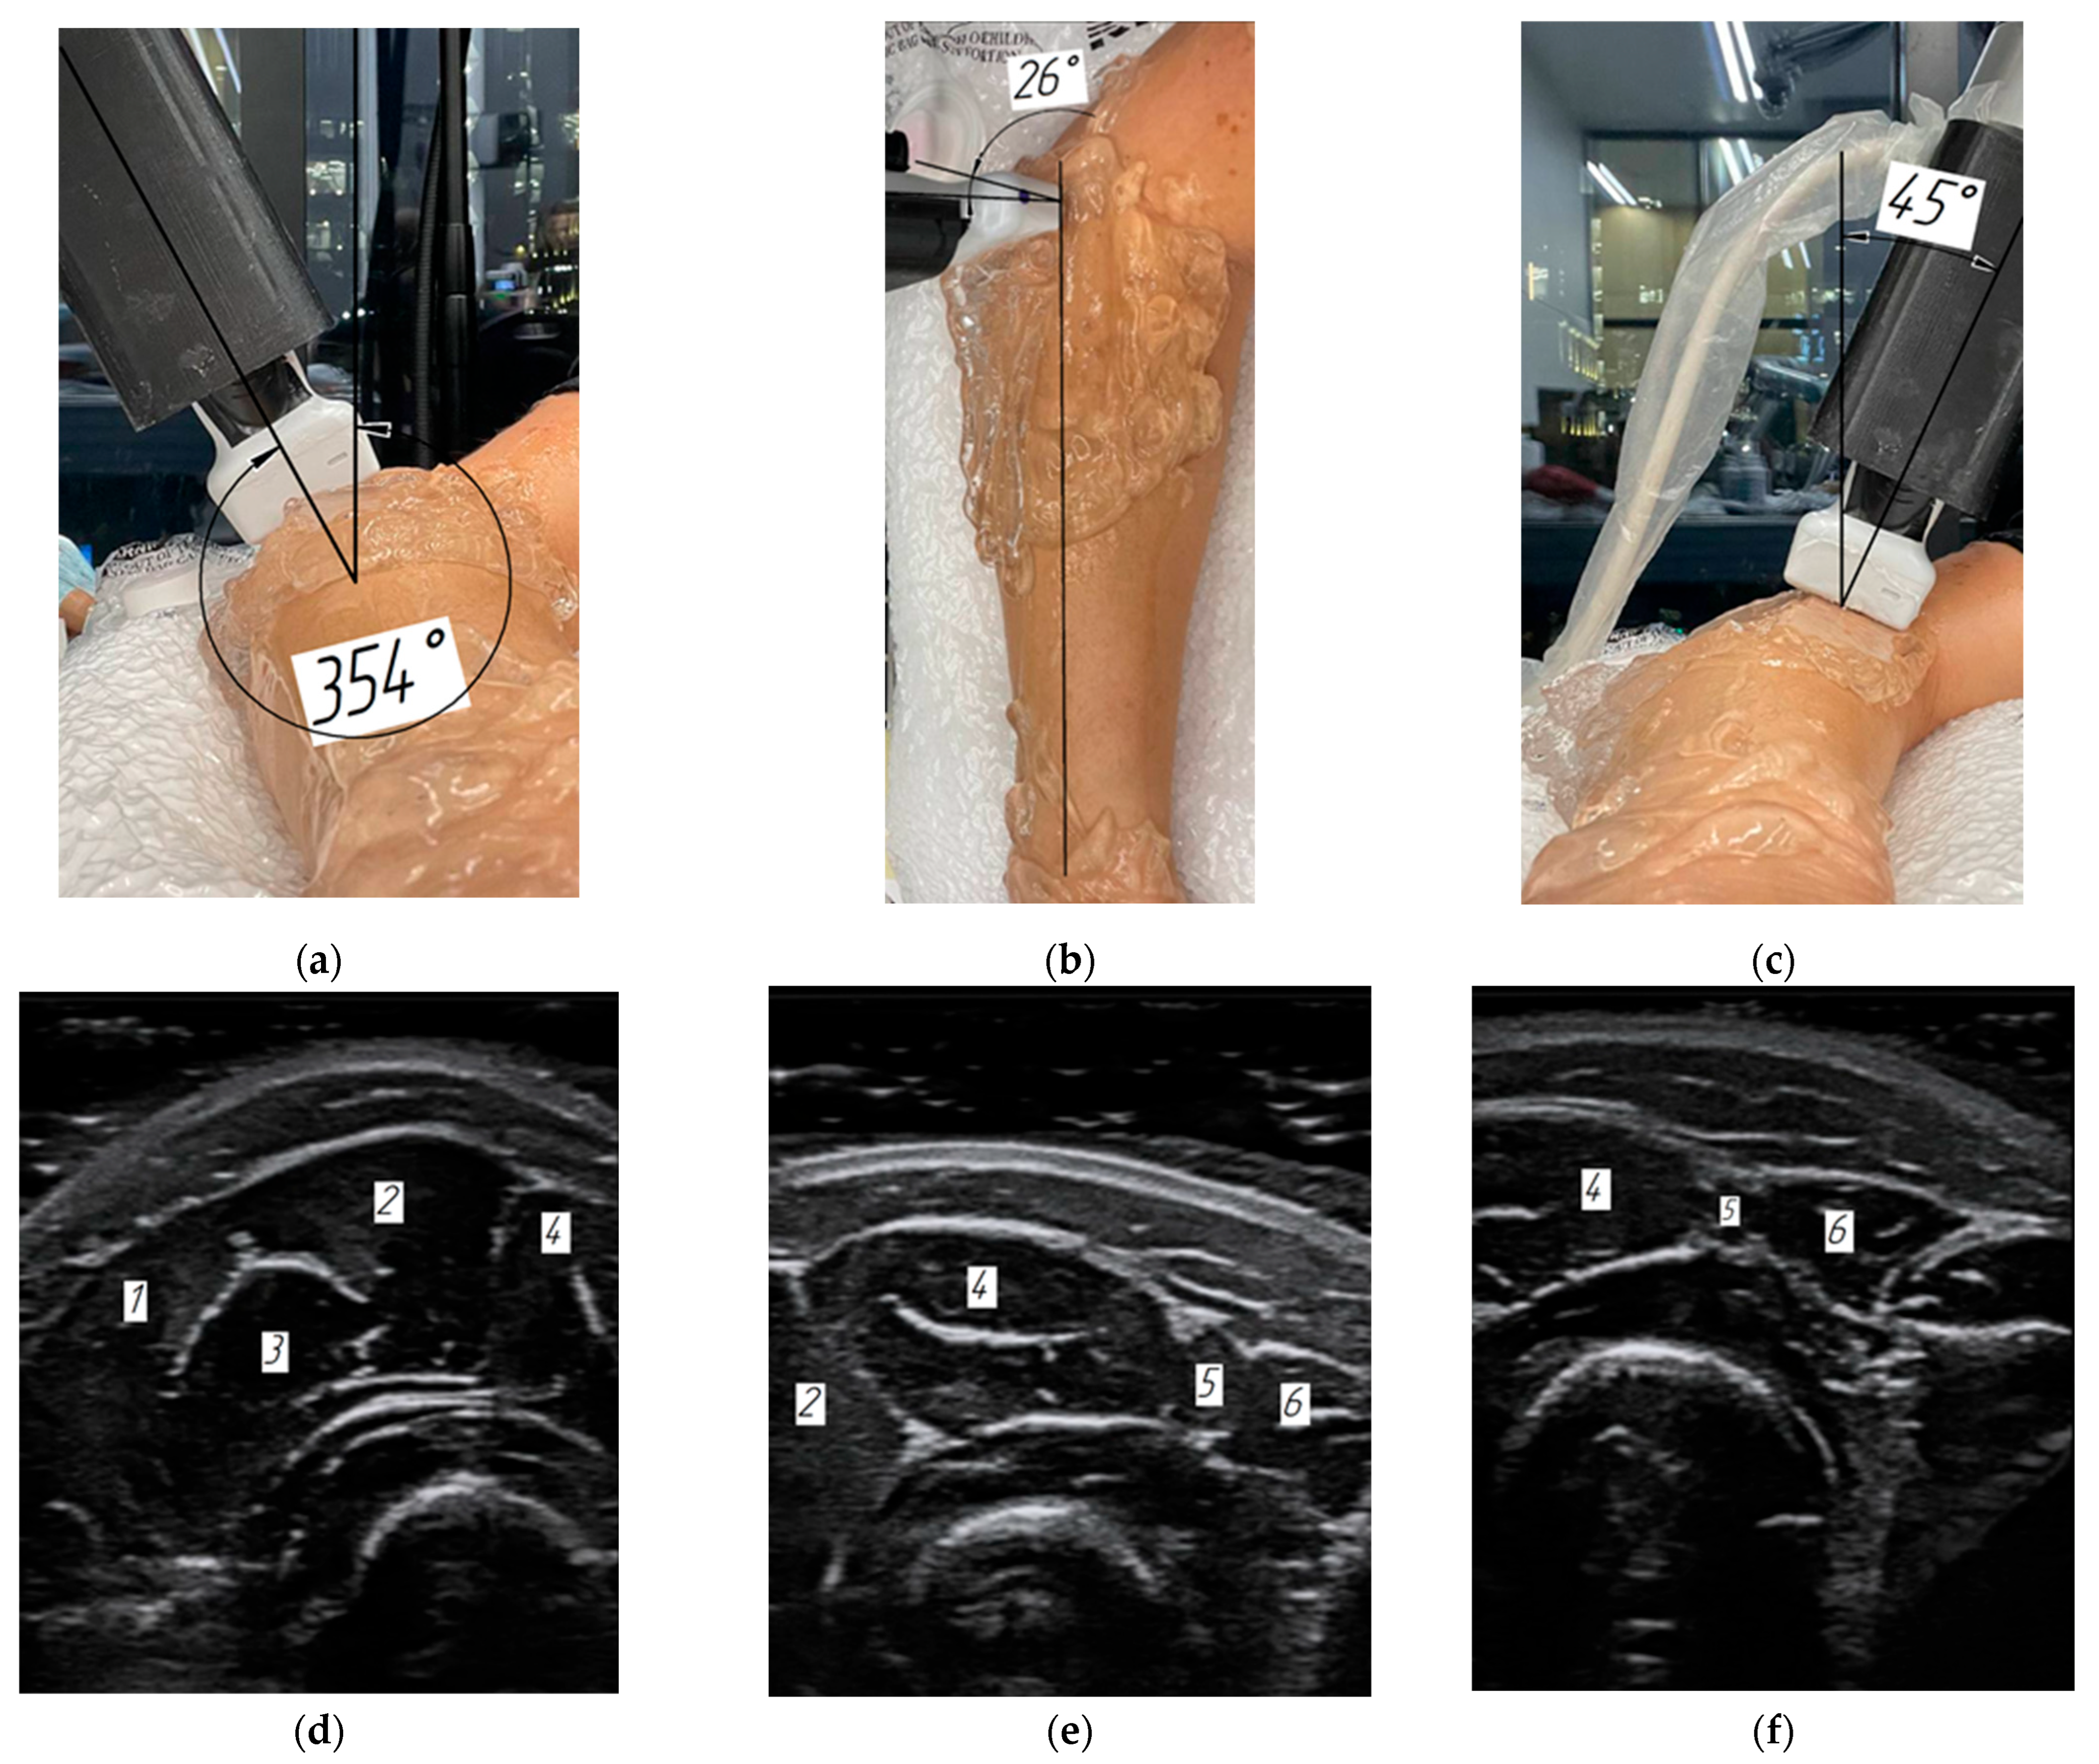

3.2. Verification of the Methodology for Constructing the Soft Tissue Volumetric Models